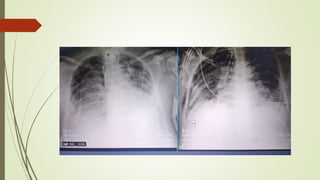

HEMOTÓRAX

1) Imagem

• Opacificação

• Não conseguimos visualizar o diafragma e a borda

cardíaca

• Observe a margem com o sinal de menisco.

• Derrame pleural no contexto agudo do trauma um

hemotórax.

2) Imagem

• Volumoso derrame pleural

• Opacificação completa do hemitórax esquerdo

• Desvio da traqueia, do coração e todas as

estruturas mediastinais para o outro lado

• Trata-se de um maciço hemotórax.